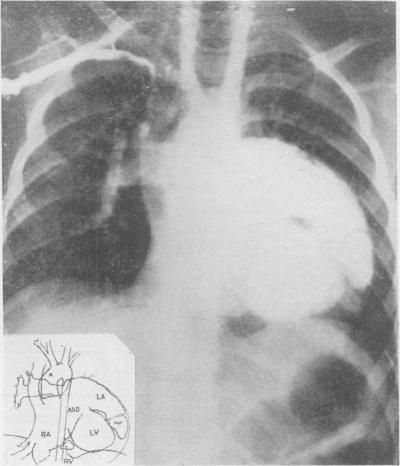

Atrial septal defects in children; an angiocardiographic study.

Circulation. 1953 Jun;7(6):819-29. doi: 10.1161/01.cir.7.6.819.